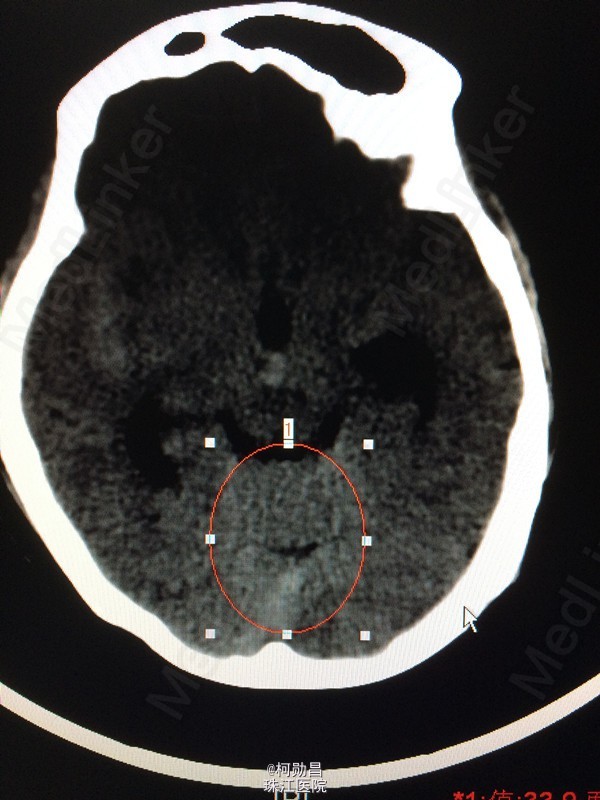

脑血管病常见病例(1)----------- 患者女,45岁,头痛,伴呕吐,CT提示蛛网膜下腔出血,DSA示大脑后动脉瘤,行介入栓塞治疗,术后恢复良好。